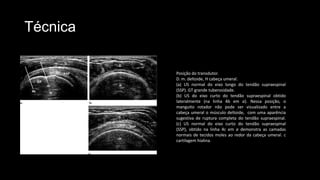

Posição do transdutor.

D. m. deltoide, H cabeça umeral.

(a) US normal do eixo longo do tendão supraespinal

(SSP). GT grande tuberosidade.

(b) US do eixo curto do tendão supraespinal obtido

lateralmente (na linha 4b em a). Nessa posição, o

manguito rotador não pode ser visualizado entre a

cabeça umeral o músculo deltoide, com uma aparência

sugestiva de ruptura completa do tendão supraespinal.

(c) US normal do eixo curto do tendão supraespinal

(SSP), obtido na linha 4c em a demonstra as camadas

normais de tecidos moles ao redor da cabeça umeral. c

cartilagem hialina.